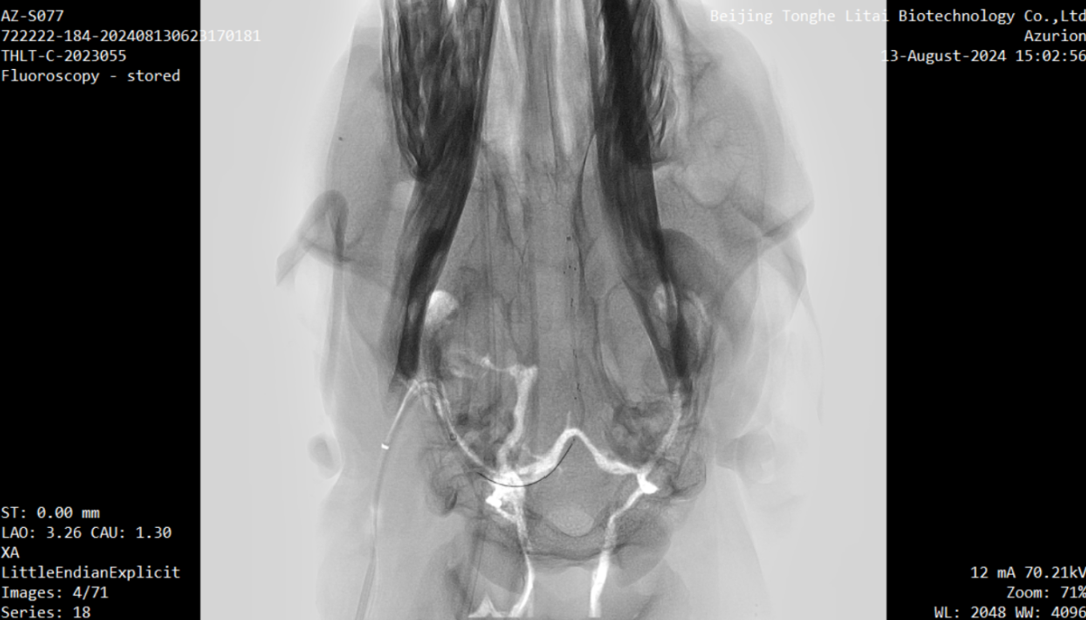

介入式脑电传感器取出过程造影 供图 南开大学

本次试验是在前期两项试验基础上取得的进一步成果。内容包括:将无线传输设备植入实验动物皮下,并将采集到的介入式脑电信号通过无线传输设备传出,实现了稳定、高效的信号传输;以及通过介入手术将先前导入羊颅内血管壁上的介入式脑机接口传感器安全取出,整个过程在DSA造影引导下进行,确保了手术过程的安全性。